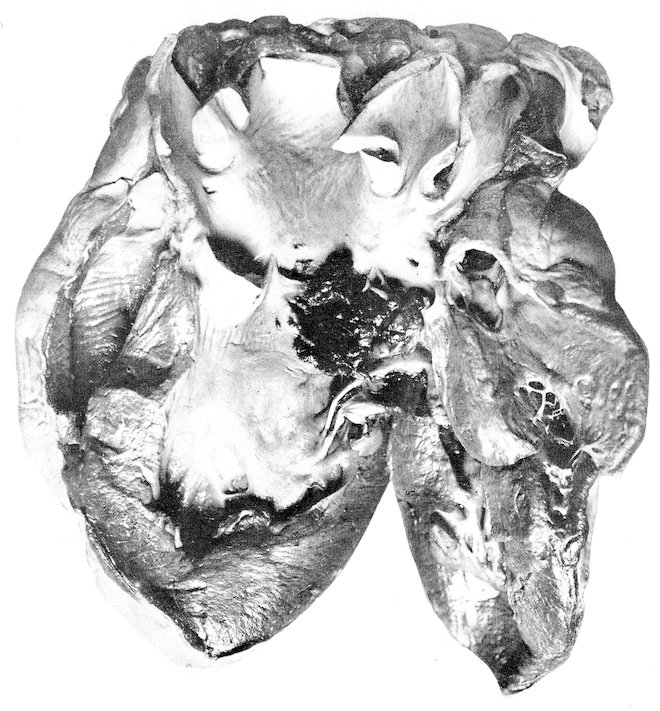

Columbæ:

Columbidæ:

Ocyphaps lophotes,